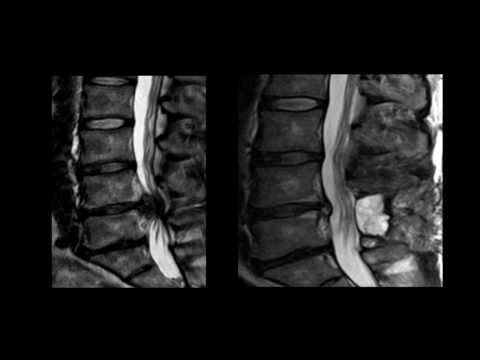

Cauda Equina Syndrome

Nick Todd Discussing Neurologic Perspective of Cauda Equina Syndrome

Lecture covering cauda equina syndrome